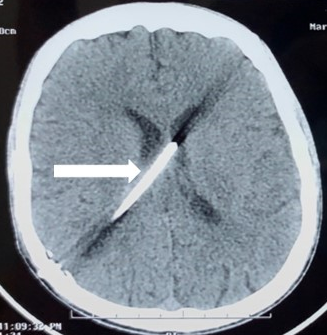

Ventriculoperitoneal (VP) shunting was done. He had further improvement in sensorium in post-operative period with CT head showing reduction in hydrocephalus (Fig. 3).

Fig. 3 Axial computed tomography of head (Post operative day 5) showing in situ ventriculoperitoneal shunt with complete reduction of the hydrocephalus.